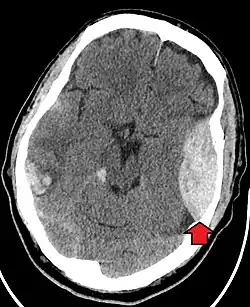

| Epidural hematoma as seen on a CT scan with overlying skull fracture. Note the biconvex shaped collection of blood. There is also bruising with bleeding on the opposite side of the brain. | |

Epidural hematomas usually appear convex in shape because their expansion stops at the skull's sutures, where the dura mater is tightly attached to the skull. Thus, they expand inward toward the brain rather than along the inside of the skull, as occurs in subdural hematomas. Most people also have a skull fracture.[3]

Non-contrast CT scan of a traumatic acute hematoma in the right fronto-temporal area. Non-contrast CT scan of a traumatic acute hematoma in the right fronto-temporal area.